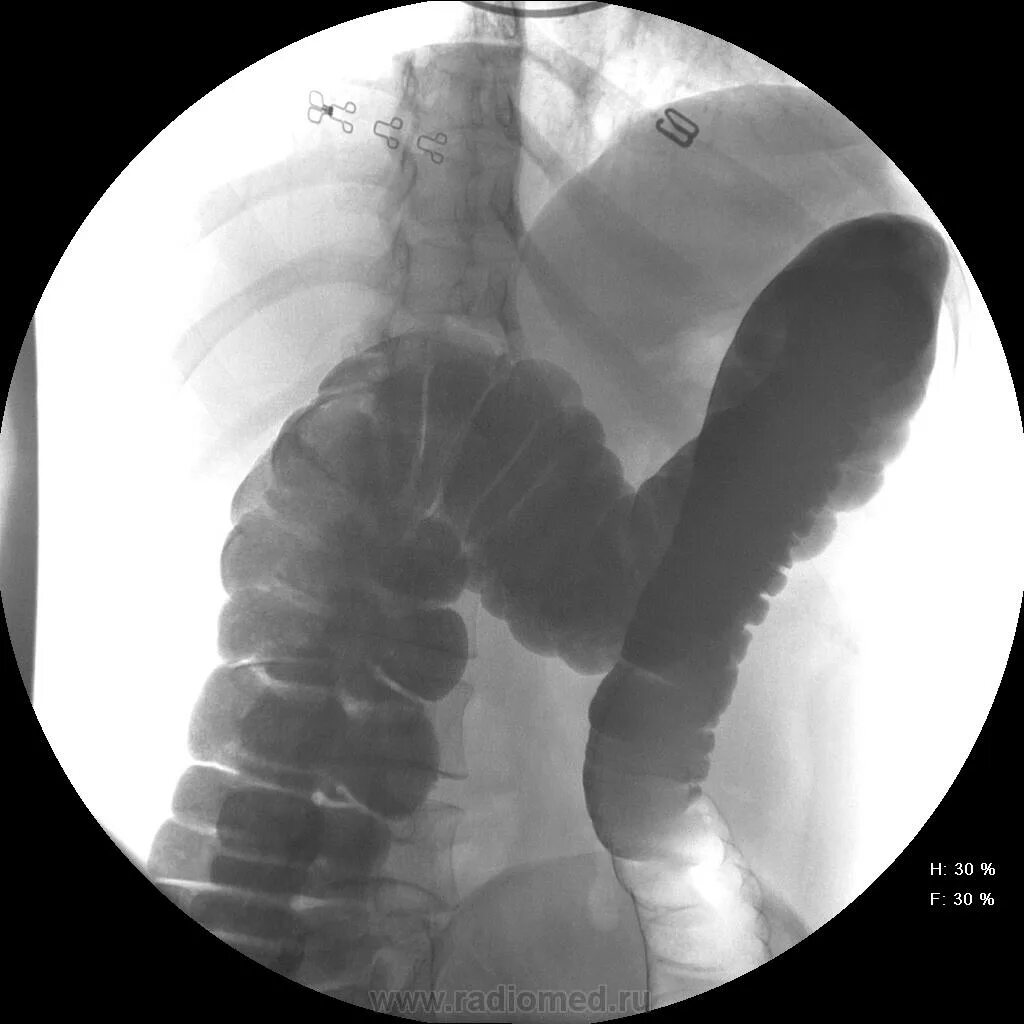

Гаустрация ободочной кишки. рентгенологическое исследование толстой кишки (ирригоскопия). гаустрация толстой кишки выражена. гаустрация сигмовидной кишки.

Гаустрация толстой кишки выражена. гаустрация сигмовидной кишки. выраженная гаустрация толстой кишки что это такое. рентгенодиагностика воспалительных заболеваний толстой кишки.

Гаустрация ободочной кишки. гаустрация толстой кишки что это. гаустрация толстой кишки рентген.